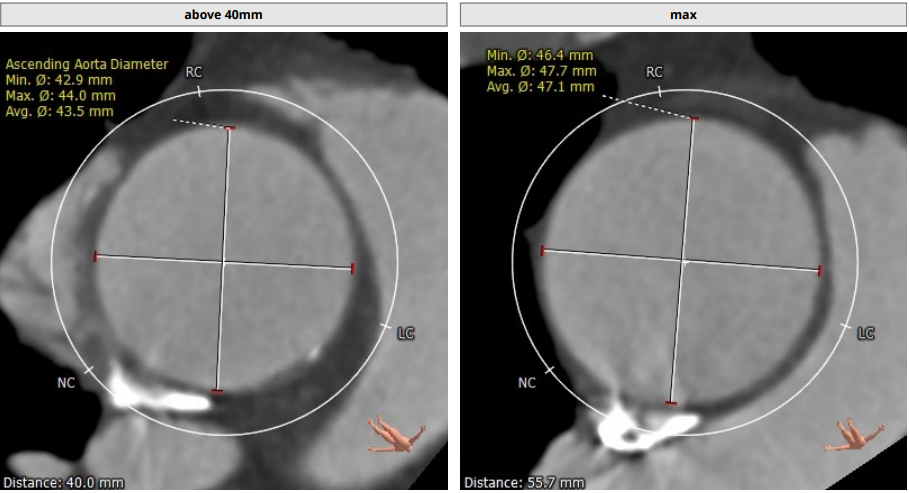

Annulus:23.3 mm,LVOT:21.9 mm,STJ:30.8 mm,Asc.AO:43.5 mm

升主动脉增宽,最宽处为 47.1 mm(55.7 mm)

TYPE1 型二叶瓣,重度钙化,钙化呈单边分布,主要集中在无冠窦侧,左右可见非钙化脊,左冠高度约 13.2 mm,右冠高度约 14 mm,法式窦结构大,STJ 高度约 19.4 mm、直径约 30.8 mm,升主动脉可见增宽,最宽处约 47.1 mm,心脏角度约 46°,左室大小可,右窦居中体位:RAO4°、CAU21°,左冠切线位:LAO2°、CAU16°。